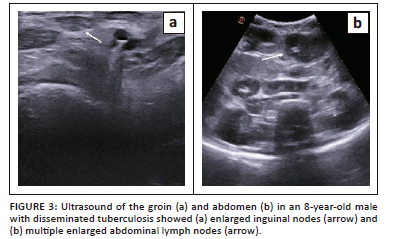

An 8-year-old male presented with complaints of high-grade fever, weight loss and abdominal distension for 1-2 months. Ultrasonography revealed hepatomegaly with multiple hypoechoic liver nodules, enlarged necrotic lymph nodes (Figure 3a and b) and gross ascites. A clinical diagnosis of disseminated tuberculosis was suggested. Biopsy from the mesenteric lymph nodes confirmed tuberculous lymphadenitis. Ascitic fluid analysis revealed elevated triglyceride content suggestive of chylous ascites.